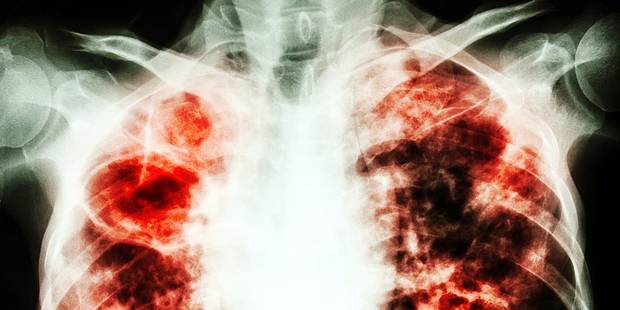

La tuberculose est une maladie provoquée par le bacille tuberculeux, qui touche le plus souvent les poumons. Elle demeure l’une des maladies infectieuses les plus meurtrières au monde. Chaque jour, plus de 4100 personnes perdent la vie à cause d’elle dans le monde et près de 28 000 personnes contractent cette maladie évitable et curable.